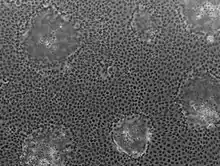

Caco-2 (from Cancer coli, "colon cancer") is an immortalized cell line of human colorectal adenocarcinoma cells. It is primarily used as a model of the intestinal epithelial barrier.[1] In culture, Caco-2 cells spontaneously differentiate into a heterogeneous mixture of intestinal epithelial cells.[1] It was developed in 1977 by Jorgen Fogh at the Sloan-Kettering Institute for Cancer Research.[2]

Microscopically, Caco-2 cell cultures show obvious heterogeneity likely reflecting the complex mixture of cells found in the epithelial lining of the large and small intestine i.e. enterocytes, enteroendocrine cells, goblet cells, transit amplifying cells, paneth cells and intestinal stem cells.[5] Over time, the characteristics of the cells used in different laboratories have diverged, introducing inter-laboratory variation.[6] Despite such heterogeneity, Caco-2 cells are used in cell invasion studies, viral transfection research, and lipid transport.[7]